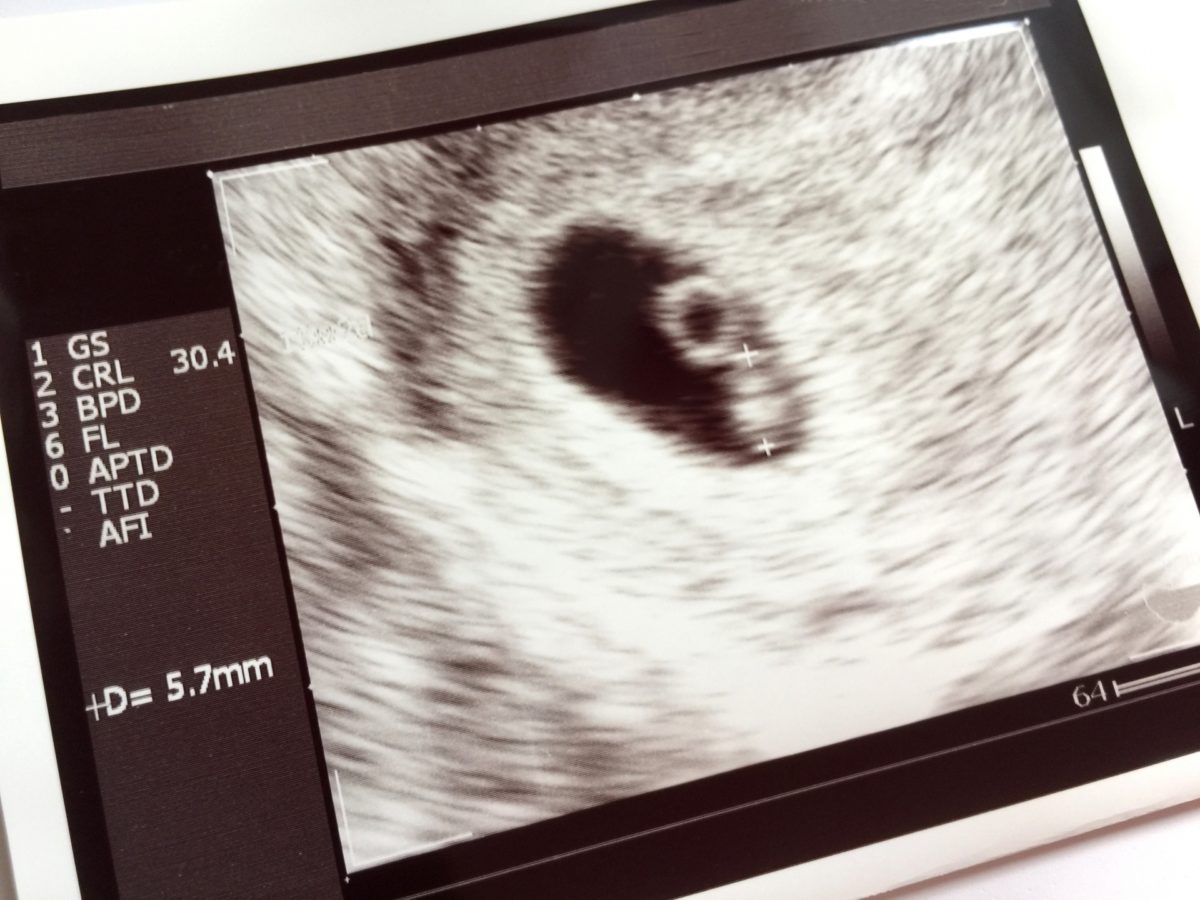

私はこれまで多くの患者さん、妊婦さんを見てきました。そんな中で思いもよらず妊娠してしまい、赤ちゃんを育てるお金もなく、また色々な事情で、仕方なく中絶を余儀なくされた方もいらっしゃいます。望まない妊娠をしてしまった女性に、手術以外で解決する選択肢が出来るかも知れない「経口中絶薬」が日本で承認されるようです。「経口中絶薬」は、すでに世界70か国以上で使われており、認められれば、国内初の中絶のためのお薬。では、どのような薬なのでしょうか?

「経口中絶薬」を使った中絶方法では、妊娠状態を薬によって中断し、人工的に陣痛を誘発して胎児を排出することで、妊娠を阻止します。